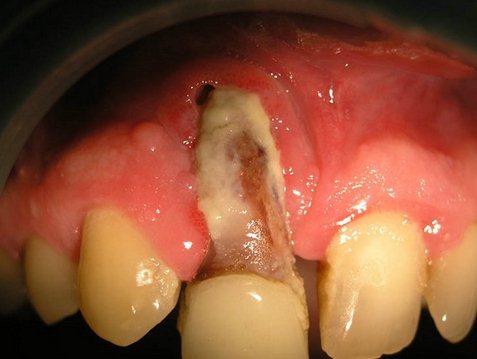

Подострый остеомиелит челюсти развивается в том случае, если отсутствовало адекватное лечение острой формы. У пациента появляются свищи и секвестры – омертвевшие участки кожи. При этом типичные симптомы воспаления могут притупиться из-за оттока жидкости и гноя, но это ничего не значит, так как воспалительный процесс в костной ткани продолжается, и с каждым днем он становится все более и более опасным.

Хронический остеомиелит челюсти – протекает длительно, причем на какое-то время у пациента имеются все внешние признаки полного выздоровления. Разумеется, это всего лишь видимость, так как воспалительный процесс продолжает развиваться и, рано или поздно, приводит к новым обострениям, образованию свищей, отторжению мертвых тканей и образованию секвестров.

В первую очередь, процесс лечения подразумевает удаление инфицированного зуба. Отметим, что остеомиелит нижней челюсти относится как раз к тем случаям, когда извлечение зуба абсолютно необходимо, иначе процесс воспаления распространится на здоровые ткани и остановить его будет куда сложнее. Также пациентам назначается ранняя периостотомия – процедура, при которой делаются надрезы надкостницы для беспрепятственного удаления экссудата (жидкости, которая образуется при развитии инфекции и отмирании тканей). Больным показан прием антибиотиков, промывание костной полости антисептиками и симптоматическая терапия. В особо тяжелых случаях врачи принимают решение о хирургическом удалении секвестров.